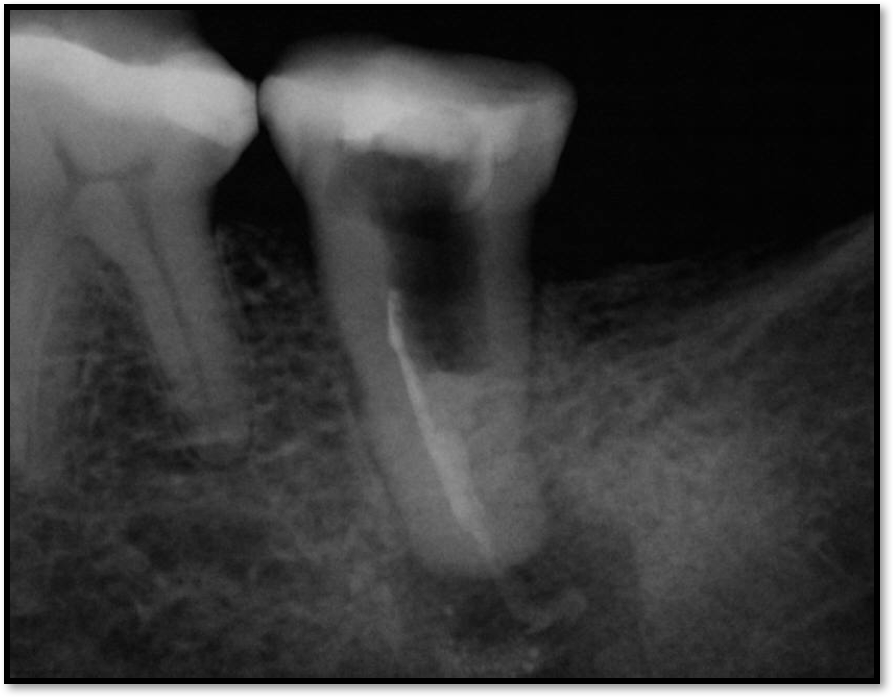

Quality of Tooth Structure

When looking at the quality of the tooth structure, the clinician is looking for indications of non-ideal conditions, such as discoloration, cracks, an undercut, and concavities. The first premolar has a concavity, but sometimes there are concavities in molars, such as the distal of the lower molar or the palatal of the maxillary molar, eg, No. 3. These are teeth that should get posts. The clinician should aim to place the post in the straighter-path canal. On tooth No. 5, for example, it is usually the palatal. There are times when the straighter option could be another canal, such as the buccal, but generally the palatal is the best option.6

Figure 2 shows a situation where the clinician excavated the tooth of a patient with decay, and it pulped out. The buccal and lingual walls were intact; however, the walls were minimal, and there were still fragments of amalgam and cracks. If the clinician prepared this tooth after building it up, the clinician would lose all the good tooth structure that was left. This tooth would likely need a post.

Fig 2. Minimal walls.

Figure 2